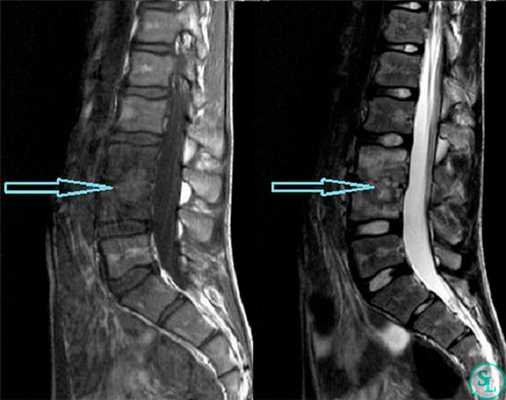

- Эпидуральный абсцесс по сути своей ограниченный процесс, однако он может захватывать несколько позвоночно-двигательных сегментов. Большинство абсцессов локализуются в области грудного (51%) и поясничного (35%) отделов позвоночника в задних отделах эпидурального пространства. На уровне шейного отдела позвоночника эпидуральные абсцессы чаще локализуются в переднем отделе эпидурального пространства.

- Методом выбора является хирургическое лечение, заключающееся в эвакуации абсцесса. При абсцессах поясничной локализации в отсутствии системных признаков воспаления и неврологического дефицита возможно консервативное лечение внутривенными антибактериальными препаратами на протяжении шести недель. Однако любые признаки развивающегося неврологического дефицита или отсутствие ответа на проводимое лечение являются показаниями к срочному оперативному вмешательству, о методиках которого мы уже говорили в этой главе.

- Твердая мозговая оболочка при абсцессах нередко окружена псевдокапсулой. Для адекватной санации абсцесса необходима тщательная и аккуратная мобилизация и удаление этой капсулы.